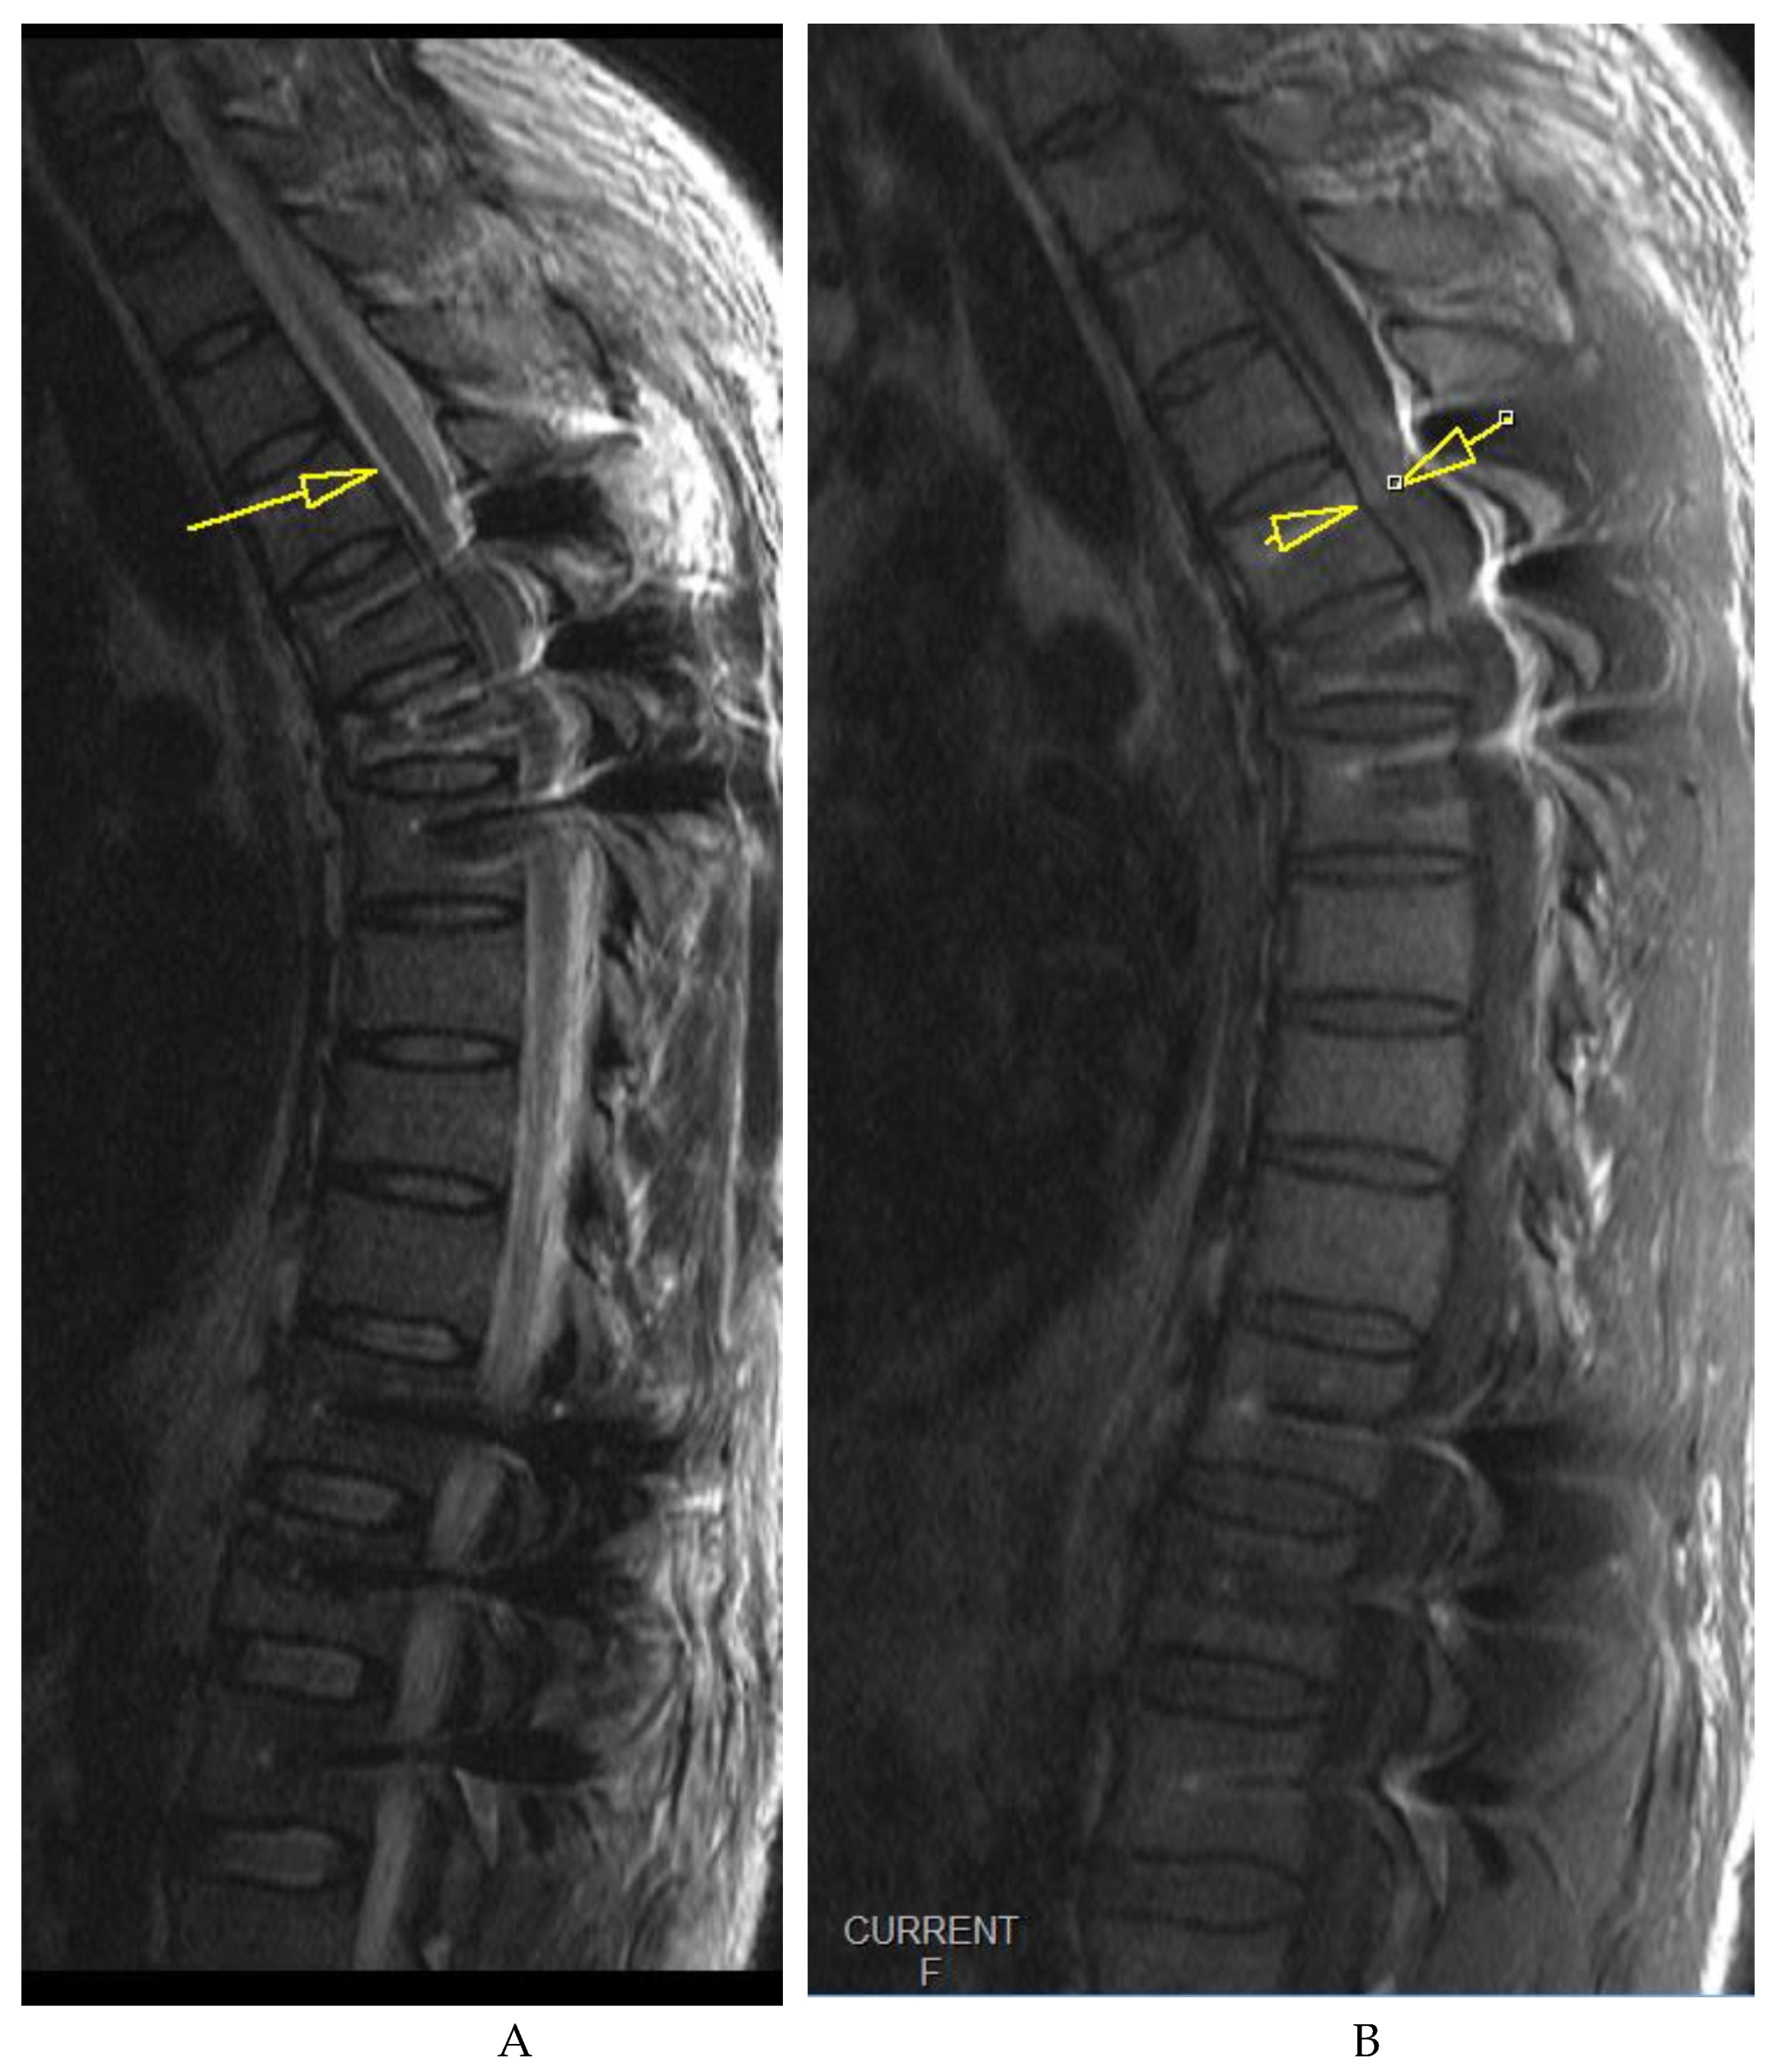

A 36-year-old male patient was admitted to our emergency trauma department with compressive Th6 and Th12 fractures as shown in Figure 1 sustained from a fall on the head and upper spine onto a soft surface. The initial examination ruled out accompanying head or any organ injury. There were no rib fractures or injuries to the extremities. The patient was neurologically normal upon admission.

On awakening from general anesthesia, the initial postoperative neurological state was without any impairment, and he was able to urinate spontaneously. Approximately 45 minutes after surgery, he began to develop signs of hypesthesia in the lower extremities, weakness in the legs, an unsettling sensation in the abdomen, and was covered with cold sweat. Due to neurological worsening, an emergency MRI of the thoracic spine was performed, which revealed a hyperacute epidural hematoma that developed at the level of the Th6 fracture and spread cranially to Th4 as shown in Figure 3. The width was measured at 7mm and compressed the spinal cord against the laminae as shown in Figure 4. Most likely the bleeding occurred from the fracture itself.

Figure 3. Emergency T2 (A) and T1 (B) weighted MRI images, midsagittal views of the thoracic spine (implant artifacts obscuring the view somewhat) show a hyperacute hematoma developing anterior to the spinal cord and spreading cranially to Th4, measuring 7mm at its thickest.